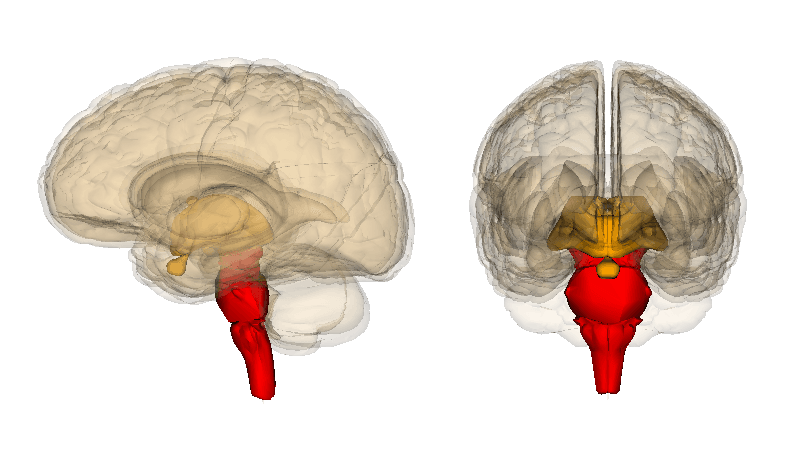

Tronco del encéfalo

El tronco del encéfalo se encuentra localizado entre el diencéfalo y la médula espinal. Está compuesto por bulbo raquídeo, protuberancia y mesencéfalo.

Esta estructura recibe la mayoría de la información motora y sensorial periférica y su función principal es integrar la información sensorial y motora.

Cerebelo

El cerebelo se encuentra en la parte posterior de cráneo, detrás del tronco, y tiene la forma de un cerebro pequeño, con la corteza en la superficie y la sustancia blanca en su interior.

Recibe e integra información principalmente de la corteza cerebral y del tronco del encéfalo. Sus funciones principales son la coordinación y adaptación de los movimientos a las situaciones, así como el mantenimiento del equilibrio.